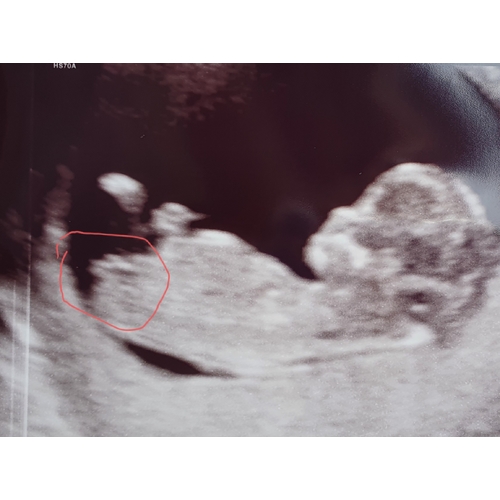

Nub was niet echt duidelijk te zien maar aantal mensen zeiden aan de hand daarvan: denk een jongen.